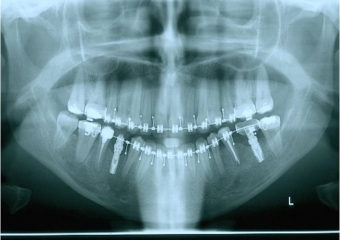

Raio x panorâmico inicial

Raio x panorâmico após a cirurgia